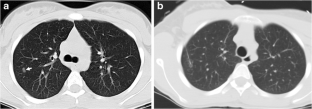

Fig. 1

Fig. 2